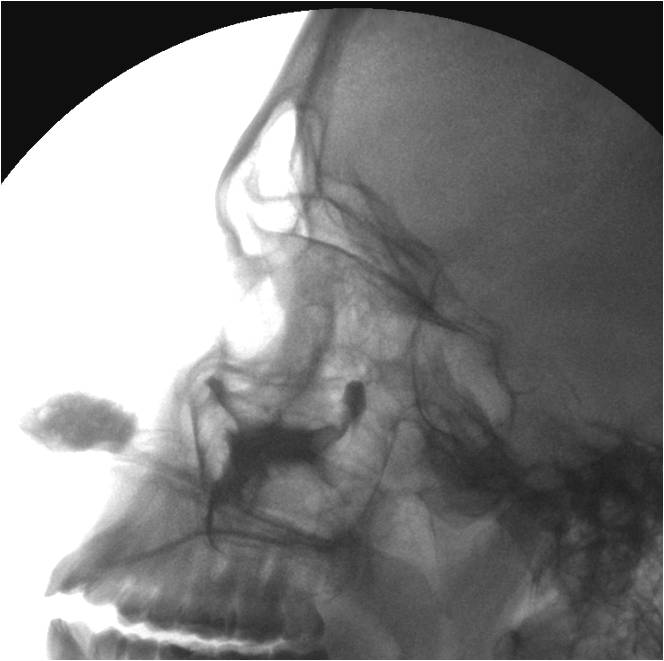

А эти иллюстрации - резкая гиперплазия слизистой оболочки в результате воспалительного процесса?

Приложения:

21.GAYM_.jpg22.GAYM_.jpg

Катенёв Валентин Львович wrote:

Да - это выраженый подушкообразный отек слизистой по всем стенкам.